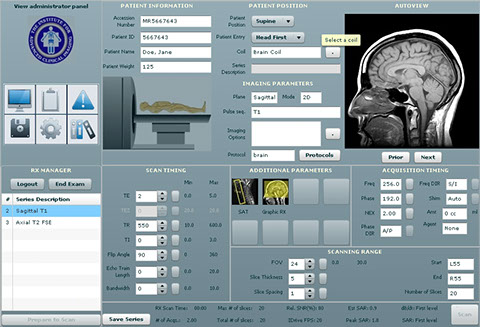

USAA ~ Safeway ~ Limited Brands ~ Macy's ~ Sears ~ Emporium ~ Nokia ~ Motorola ~ Samsung ~ LG ~ BlackBerry ~ HTC ~ Wal-Mart Stores ~ CVS ~ Best Buy ~ Rite Aid ~ Nike ~ GAP ~ J. C. Penney ~ Chevron ~ General Electric ~ AT&T ~ Hewlett-Packard ~ Bank of America Corp. ~ Citigroup ~ Berkshire Hathaway ~ International Business Machines ~ McKesson ~ Kaiser Permanente ~ Kaiser Hospitals ~ U.C.S.F ~ Stanford University School of Medicine/Medical Center ~ Sutter Healthcare ~ California Pacific Medical Center ~ San Francisco General Hospital And Medical Center ~ San Francisco VA Medical Center ~ U.S. Department of Transportation ~ U.S. Department of Homeland Security ~ Exar ~ Boeing ~ AIS ~ Siemens ~ Kaiser People Solutions ~ Cardinal Health ~ Procter & Gamble ~ UnitedHealth Group ~ Kroger ~ Marathon Oil ~ Costco Wholesale ~ Home Depot ~ Target ~ Johnson & Johnson ~ Morgan Stanley ~ State Farm Insurance ~ Dell ~ Boeing ~ Microsoft ~ Walgreen ~ United Technologies ~ Dow Chemical ~ MetLife ~ Wells Fargo ~ United Parcel Service ~ Caterpillar ~ Lowe's ~ Sears Holdings ~ Cisco Systems ~ Johnson Controls ~ FedEx ~ Intel ~ Sysco ~ Comcast ~ Coca-Cola ~ American Express ~ Aetna ~ Motorola ~ Allstate ~ Prudential Financial ~ Tyson Foods ~ Staples ~ Delta Air Lines ~ City and County of Sacramento ~ City and County of San Francisco ~ City and County Oakland ~ San Jose International Airport ~ JFK International Airport